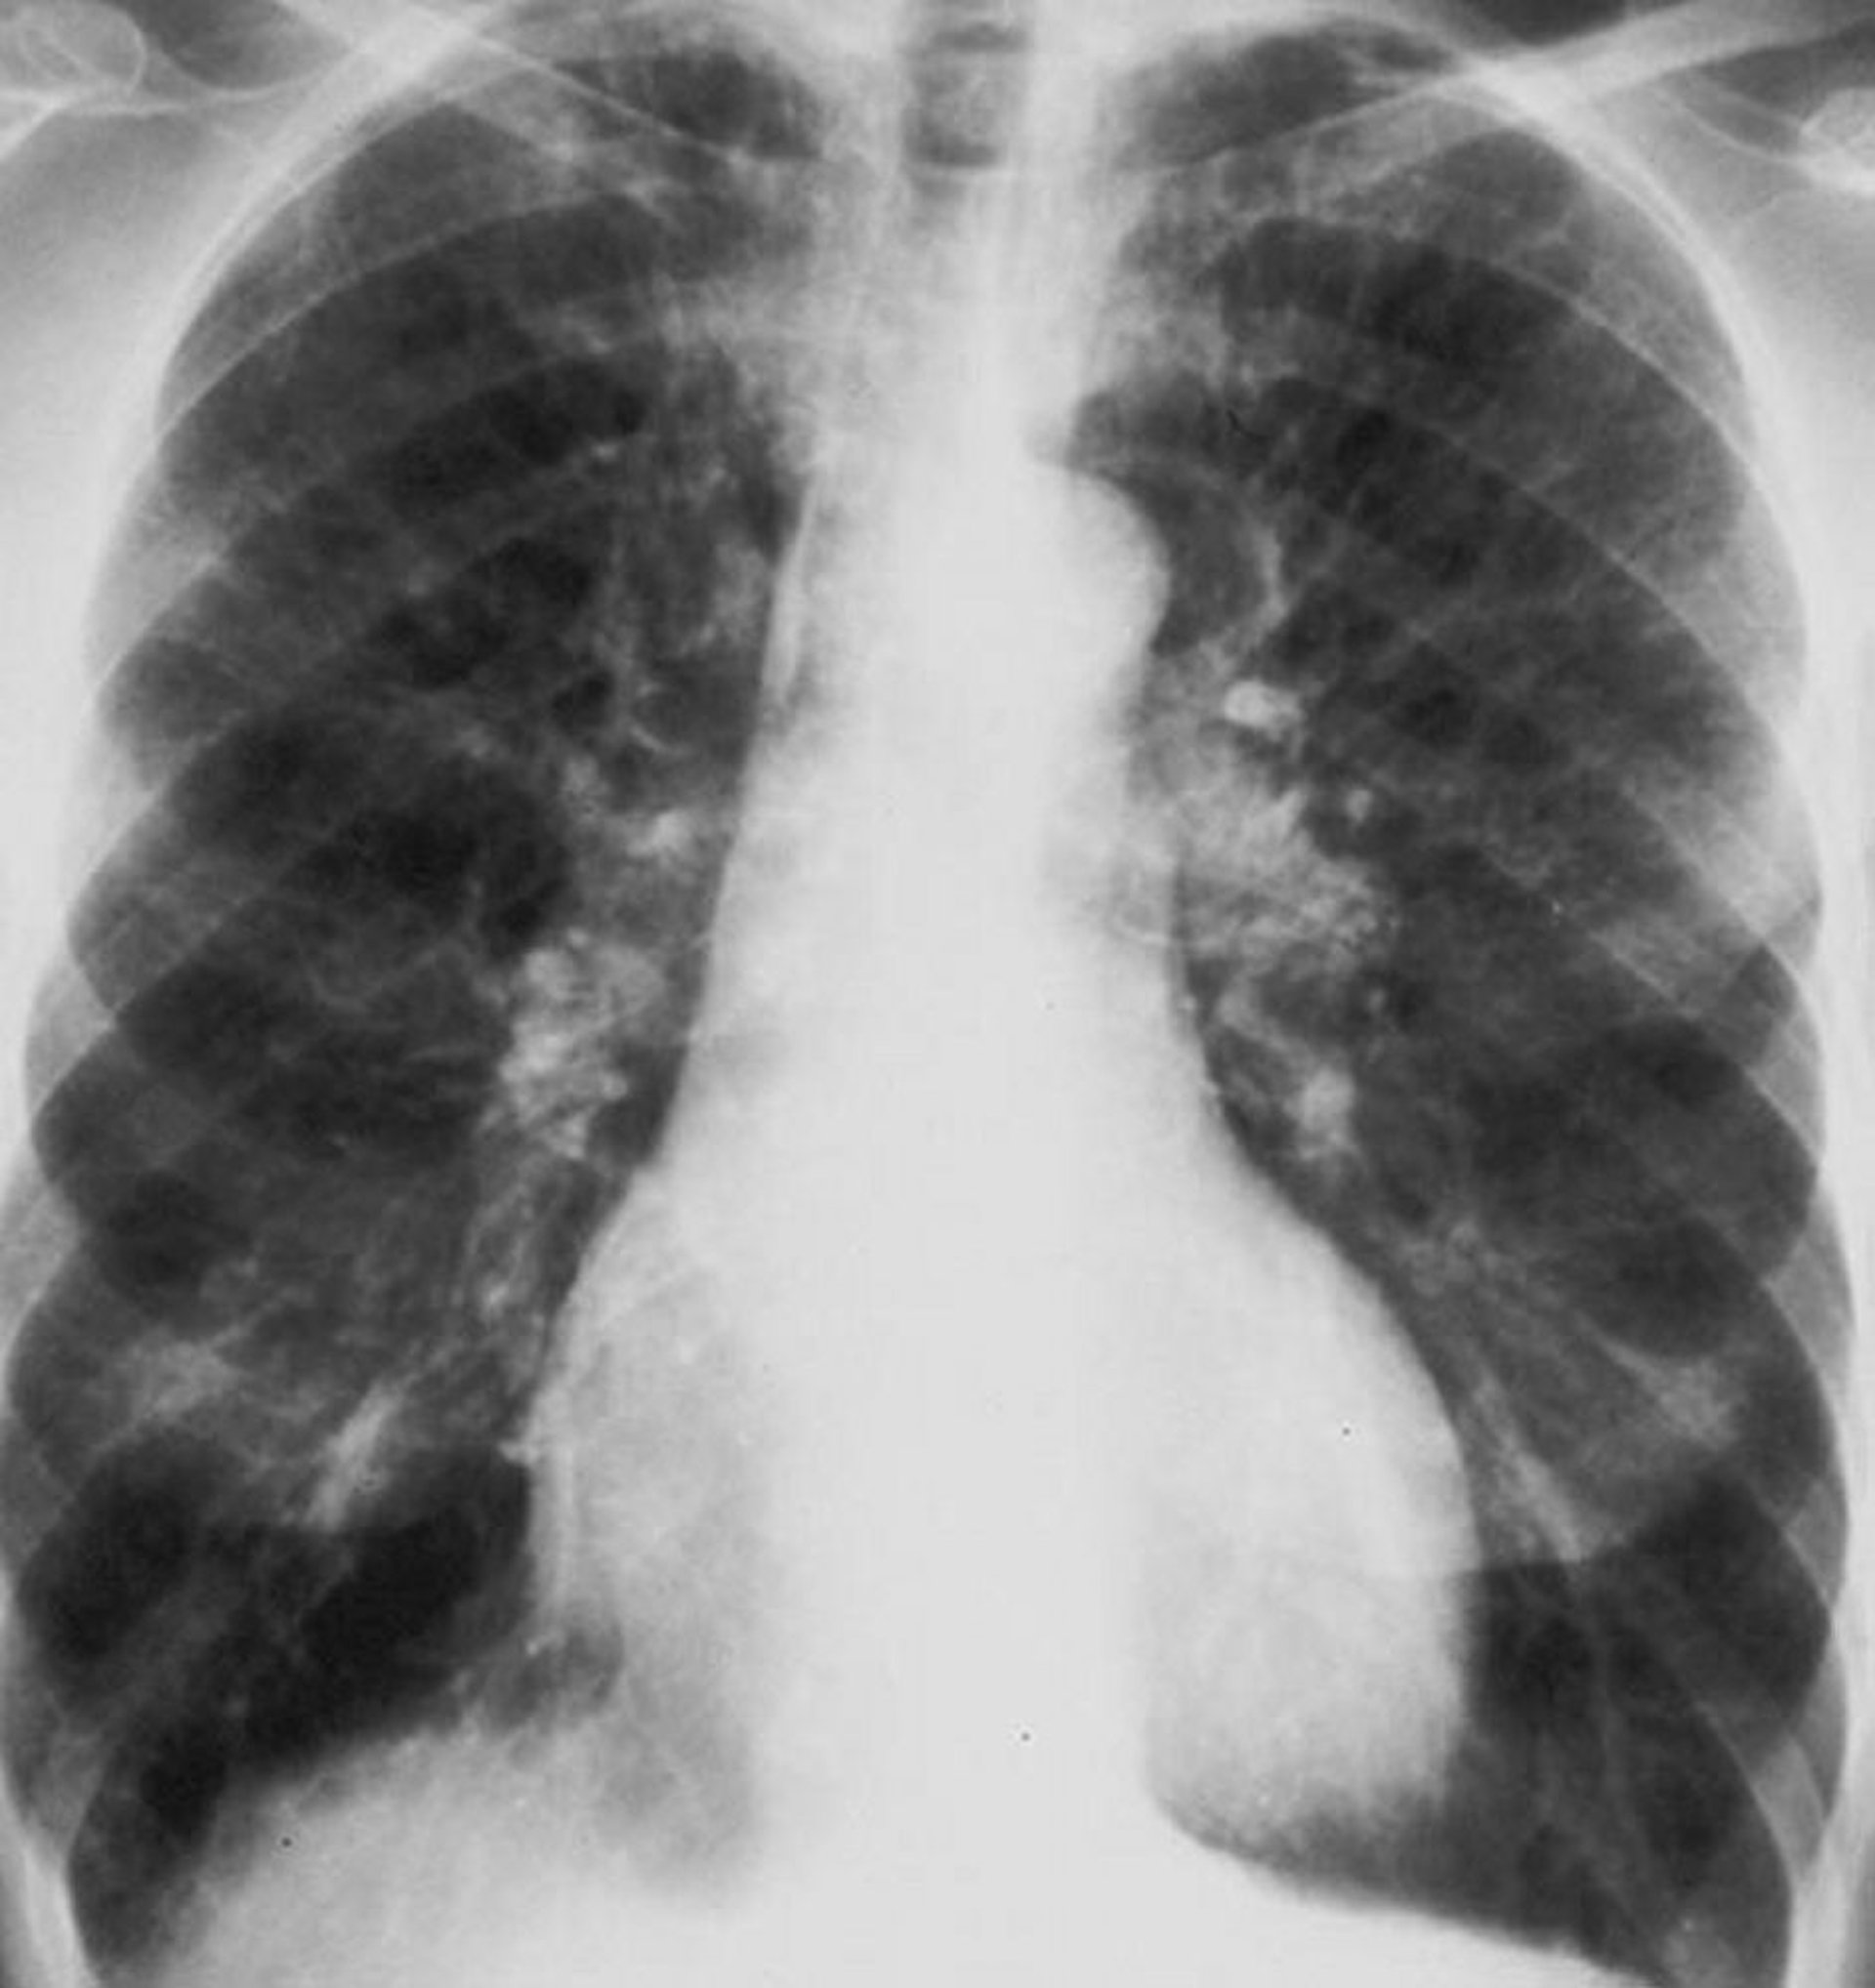

Bệnh phổi tắc nghẽn mạn tính (phim X-quang phổi)

Phim X-quang phổi của bệnh nhân mắc bệnh phổi tắc nghẽn mạn tính (COPD). Phổi bị căng phồng, cơ hoành bị xẹp, các dấu hiệu mạch máu tăng lên và kích thước tim tăng nhẹ.

Được sự cho phép của nhà xuất bản. Theo Barnes P. Trong Bone's Atlas of Pulmonary and Critical Care Medicine. Biên tập bởi J Crapo. Philadelphia, Current Medicine, 2005.